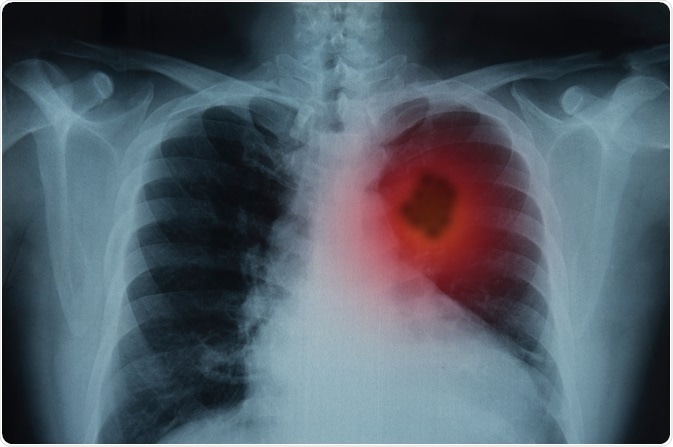

Image Credit: Create Jobs 51/Shutterstock.com